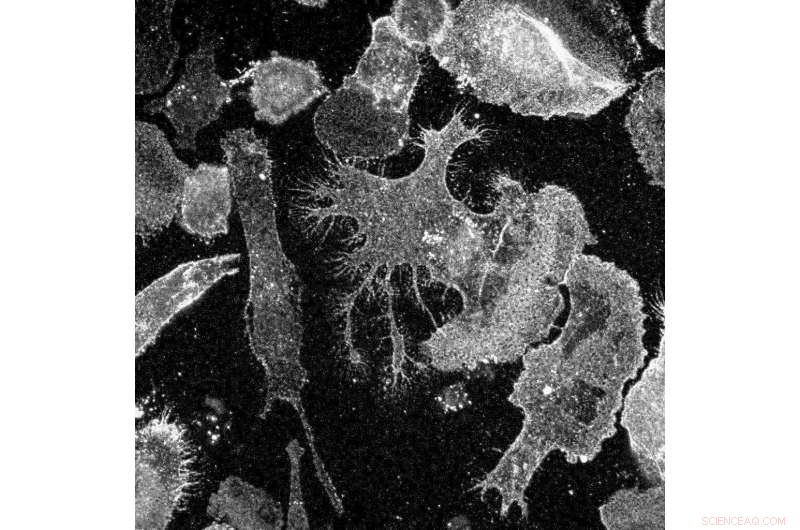

Dopaminergic neurons growing in a culture dish (20x magnification). A skin biopsy from a patient with Parkinson's disease was reprogrammed into induced pluripotent stem cells. The stem cells were then differentiated into dopaminergic neurons (green), the same cells that are lost in Parkinson's disease patients. Work is under way to use these cells as a replacement for lost neurons as a treatment for the disease. Credit: Aspen Neuroscience